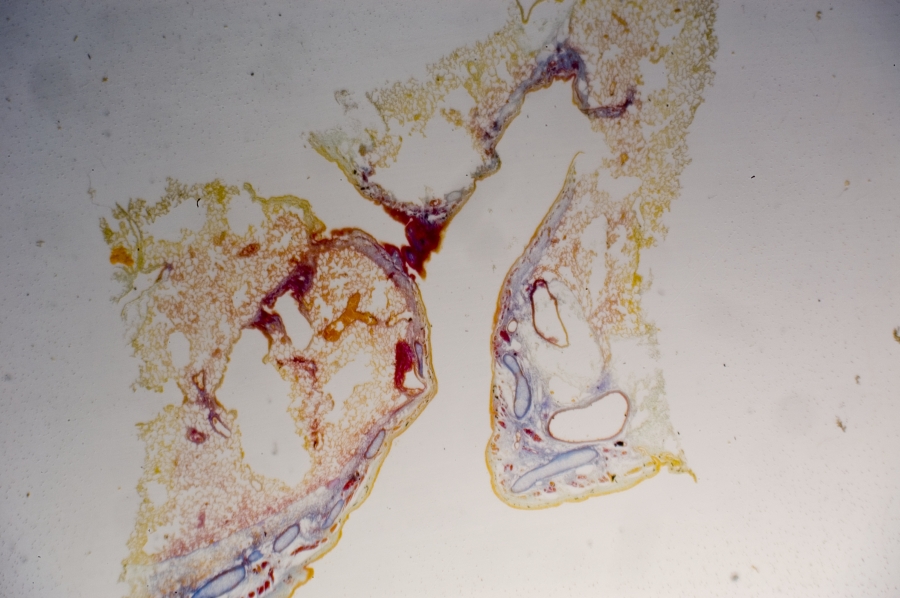

Image Filename: 36931_4524-1

36931_4524-1

container invno 36931

specimen id 4524